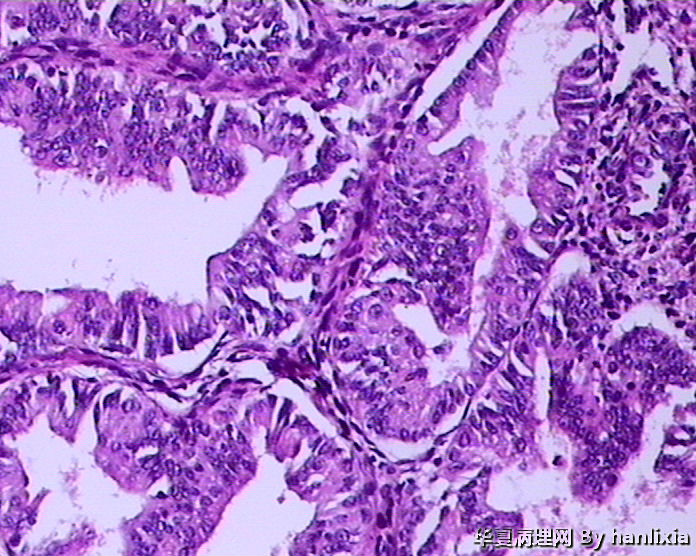

• 子宫内膜图2

图2

标签:45岁女性 闭经1年 阴道出血10余天 行诊刮术。

支持复杂性增生伴不典型增生,细胞核淡染、核变圆,并见明显的核仁,有细胞学的不典型性

复杂性伴非典型增生

腺体密集,背靠背及共壁现象,腺体有成角,腺上皮增生呈多层,有内折,腺体与间质比例大于1:1.

子宫内膜复杂性增生伴中-重度不典型增生,图1-2可疑癌变